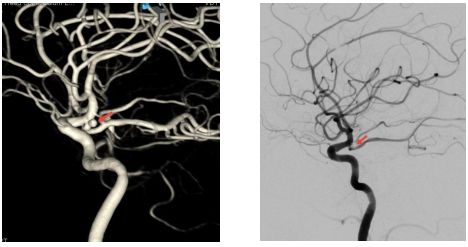

与半年手术前(左图)相比,复查脑血管造影(右图)见左侧后交通动脉瘤致密栓塞无复发,左侧后交通动脉畅通